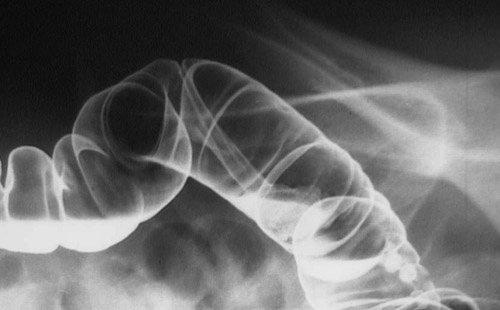

Image 4.2

The gross lesion here is from another case of a patient with several of these lesions. The barium enema view below demonstrates a colonic polyp. The head of the polyp is partially obscured by the pool of barium contrast in which it rests.